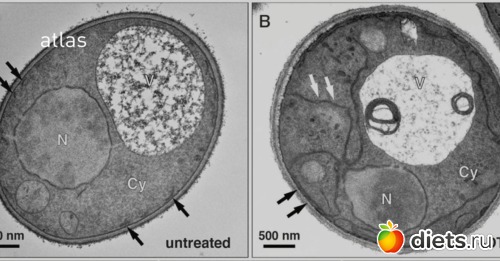

Для своих испытаний японский ученый использовал пекарские дрожжи — эукариотический организм (клетки которого содержат ядро), процесс аутофагии в котором можно наблюдать в микроскоп. В результате различных экспериментов и генных модификации Ёсинори Осуми определил белки и гены, которые участвуют в аутофагии.